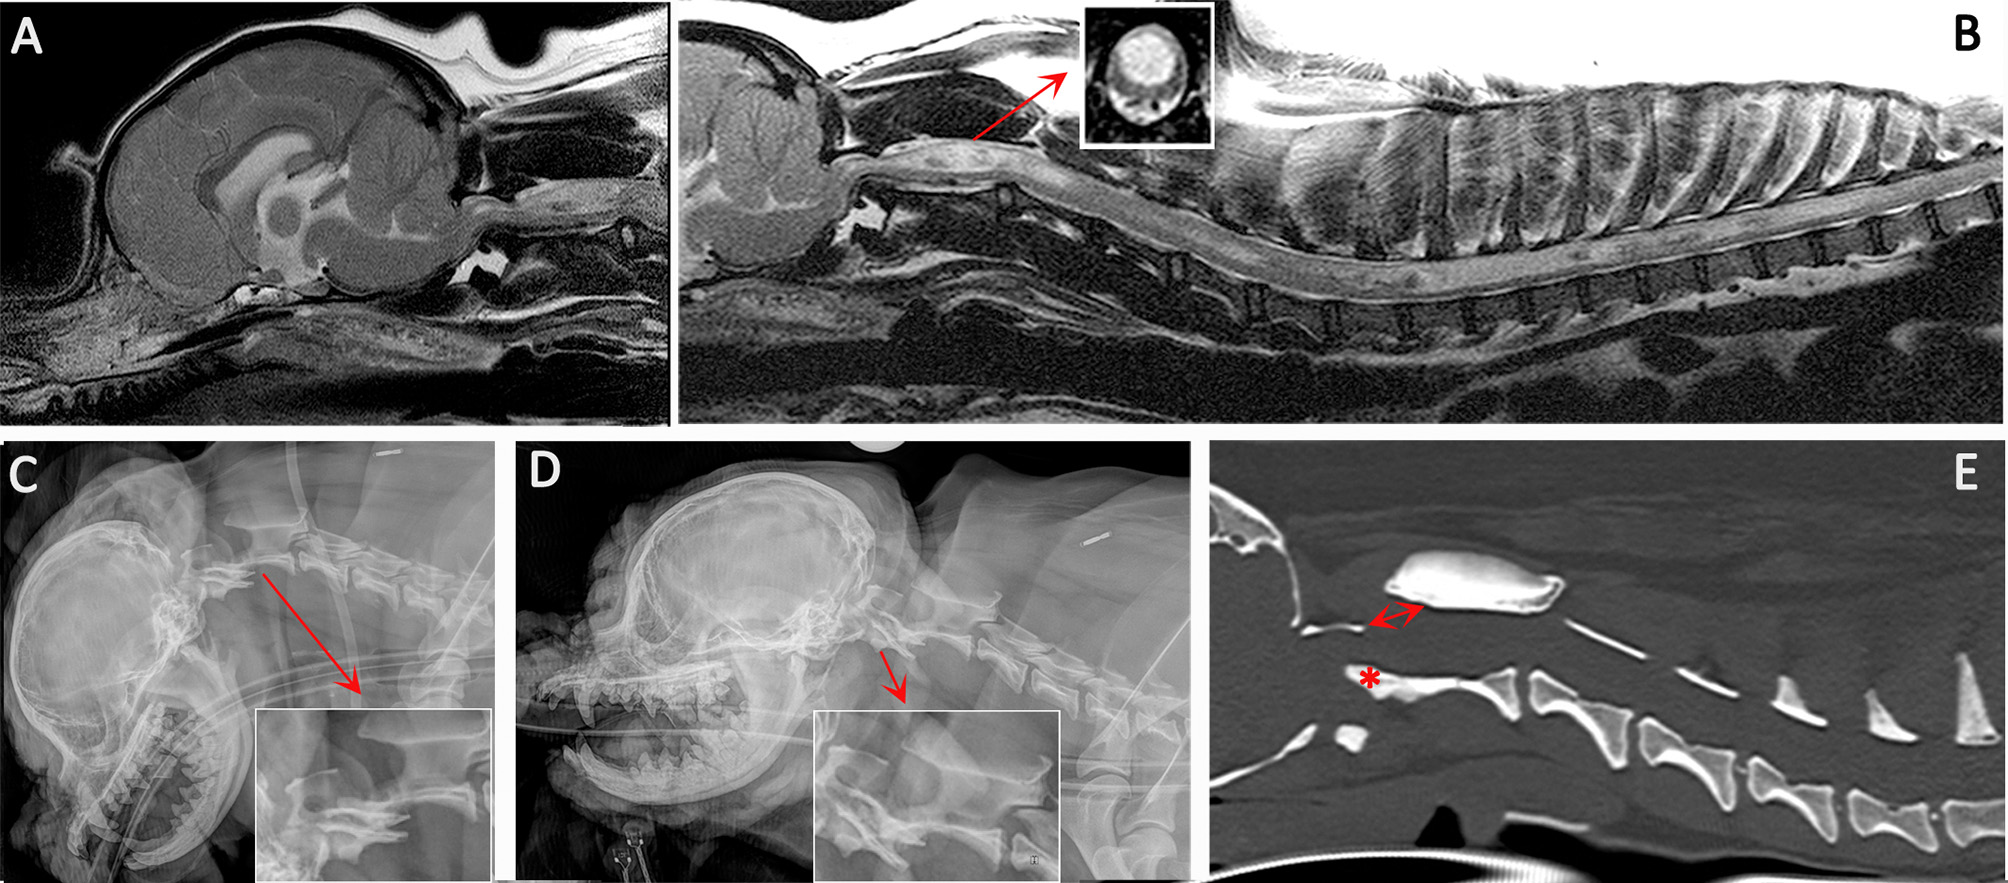

Figure 3

Diagnostic imaging from a 5 year female CKCS presented with lethargy, ataxia, cervicotorticollis, and phantom scratching and following MRI diagnosed with symptomatic CM and SM. (A) T2-weighted mid-sagittal MRI of the brain and cranial cervical spinal cord. (B) T2- weighted mid sagittal MRI of the hindbrain and spine from C1 to T10. (C) Lateral skull and cervical spinal radiograph flexed at the atlantoaxial joint. (D) Lateral skull and cervical spinal radiograph extended at the atlantoaxial joint. (E) CT reformatted in the sagittal plane of the skull and cervical spine. MRI imaging (A,B) confirmed CM and SM with a large mid cervical SM involving the superficial dorsal horn thus explaining the cervicotorticollis and phantom scratching (insert). MRI also suggested atlantoaxial instability with spinal cord compression by the odontoid peg. Atlantoaxial instability was confirmed by a dynamic radiographic study (C,D). The CT was obtained for pre-surgical planning. The dorsal displacement of the odontoid peg (asterisk) and dorsal opening (arrow) between the atlas and axis can be appreciated (Siemens Magnetom Symphony, A Tim System, 1.5 T, Erlangen, Germany; Toshiba Aquilion Prime 160 slice, Otawara, Japan).